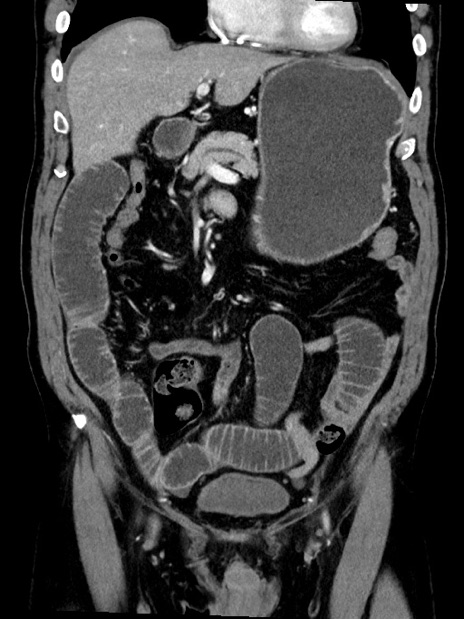

症例35(冠状断像)

【症例】70歳代 男性

【主訴】腹部膨満、嘔吐

【現病歴】昨日より腹部膨満感出現。本日増悪し、仙痛出現。嘔吐あり、受診。

【既往歴】糖尿病、胆摘後

【身体所見】BP 149/80mmHg、HR 74/min、BT 35.9℃、腹部:膨満、軟、圧痛なし。腸雑音減弱あり。上腹部正中切開瘢痕あり。

【データ】WBC 13500、CRP 1.72